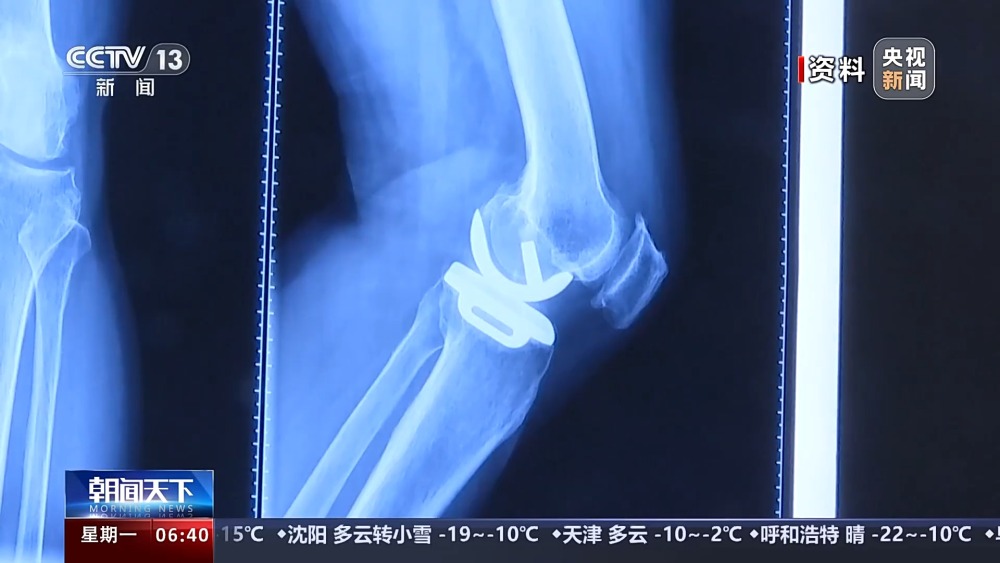

目前,我國(guó)有超過1億人患有骨關(guān)節(jié)炎,65歲以上人群中,骨關(guān)節(jié)炎發(fā)病率接近50%。以前,嚴(yán)重骨關(guān)節(jié)炎患者主要通過膝關(guān)節(jié)置換手術(shù)來維持行走等基本功能。膝關(guān)節(jié)置換手術(shù)存在術(shù)后關(guān)節(jié)僵硬、長(zhǎng)期疼痛等問題。保膝治療包括藥物、理療等保守治療,以及手術(shù)治療。

保膝手術(shù)主要包括截骨術(shù)和單髁置換術(shù),其中截骨術(shù)在解決患者疼痛癥狀的同時(shí),阻止下肢異常應(yīng)力對(duì)膝關(guān)節(jié)的進(jìn)一步損傷,膝關(guān)節(jié)內(nèi)所有軟骨韌帶、半月板都得到了保留。內(nèi)側(cè)單髁置換術(shù),使膝關(guān)節(jié)外側(cè)健康的軟骨和半月板得到了保留,膝關(guān)節(jié)內(nèi)外側(cè)的韌帶維持原有狀態(tài),患者康復(fù)后,擁有正常的膝關(guān)節(jié)功能。